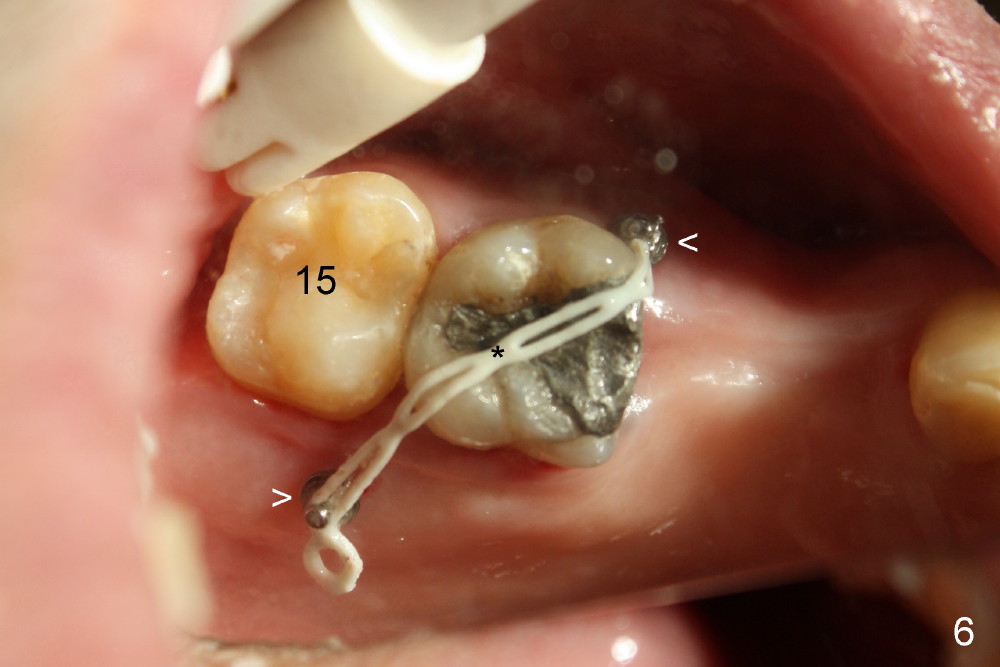

给植牙(图四箭头)装上4.5(直径)x5 (高度)mm基牙(A)时,病人咬合不对:上下第二磨牙(#15, 18)之间有空间。直感基牙太长了,必须磨短,但是磨短坚硬的钛合金基牙,可不容易,而且这次要磨除不少,越磨越老火(upset),突然意识到自己犯一个严重错误。终于上下牙齿能碰到(图五镜影像mirror image),但是还没有足够间隙为植牙制作牙冠。这时很容易看出上颌第一磨牙往下面伸长(图五),如果再磨短基牙,牙冠固位可能不好,所以唯一方法便是把上颌第一磨牙往上面压(intrusion),需要做牙齿矫正,而且使用微型植牙(图五至图七箭头;*:橡皮筋持续牵引磨牙往上移动)。